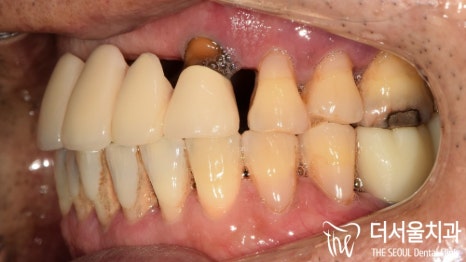

우선 환자의 초진 사진을 살펴볼까요?

음.. 한눈에 봐도 심하게 손상된 치아를

육안관찰에서 확인할 수 있었습니다.

이곳은 이전에 치료를 받았던 곳인데요.

오래된 것도 그렇고,

제대로 된 관리를 하지 못해

외관은 물론이며 치조골까지 소실이 되어있네요.